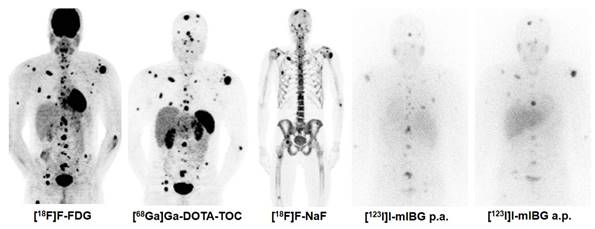

Figure 2

Combination Treatment of PRRT with [131I]I-mIBG. [68Ga]Ga-DOTA-TOC, [18F]F-FDG, [131I]I-mIBG, and [18F]F-NaF imaging in a 30 year old male patient with metastatic pheochromocytoma (functional tumour). In such rare cases, the combination treatment of PRRT with [131I]I-mIBG can be considered based on tumour accumulation of both thera(g)nostics.